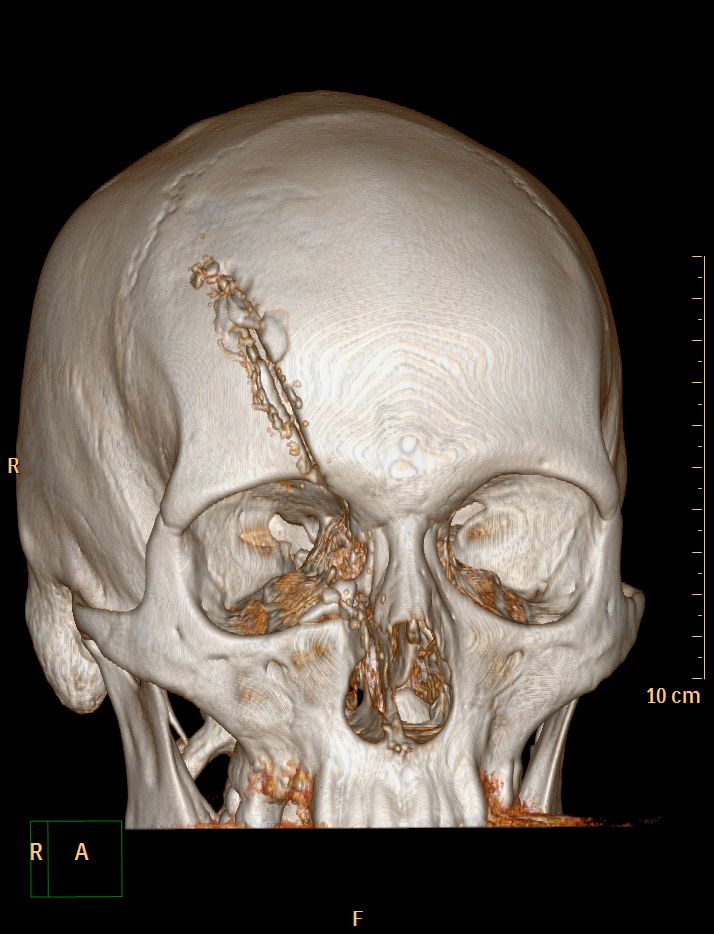

Accident de scie circulaire